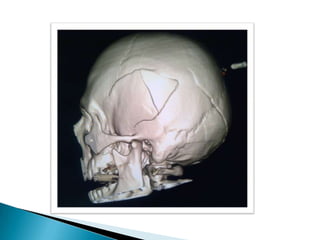

   TC cerebro: Presencia de trazo fracturario a

nivel occipital, temporo-parietal izquierda y

hundimiento de región derecha.

TC cerebro: Presencia de trazo fracturario a nivel occipital, temporo-parietal izquierda y hundimiento de región derecha.  Imagen hiperdensa en región fronto- temporo-parietal izquierda, con desplazamiento de la línea media y borramiento de ventrículos laterales compatible con hemorragia subdural.  Hiperdensidad compatible con hemorragia subaracnoidea.  Cefalohematoma que recorre toda la zona occipital y temporal